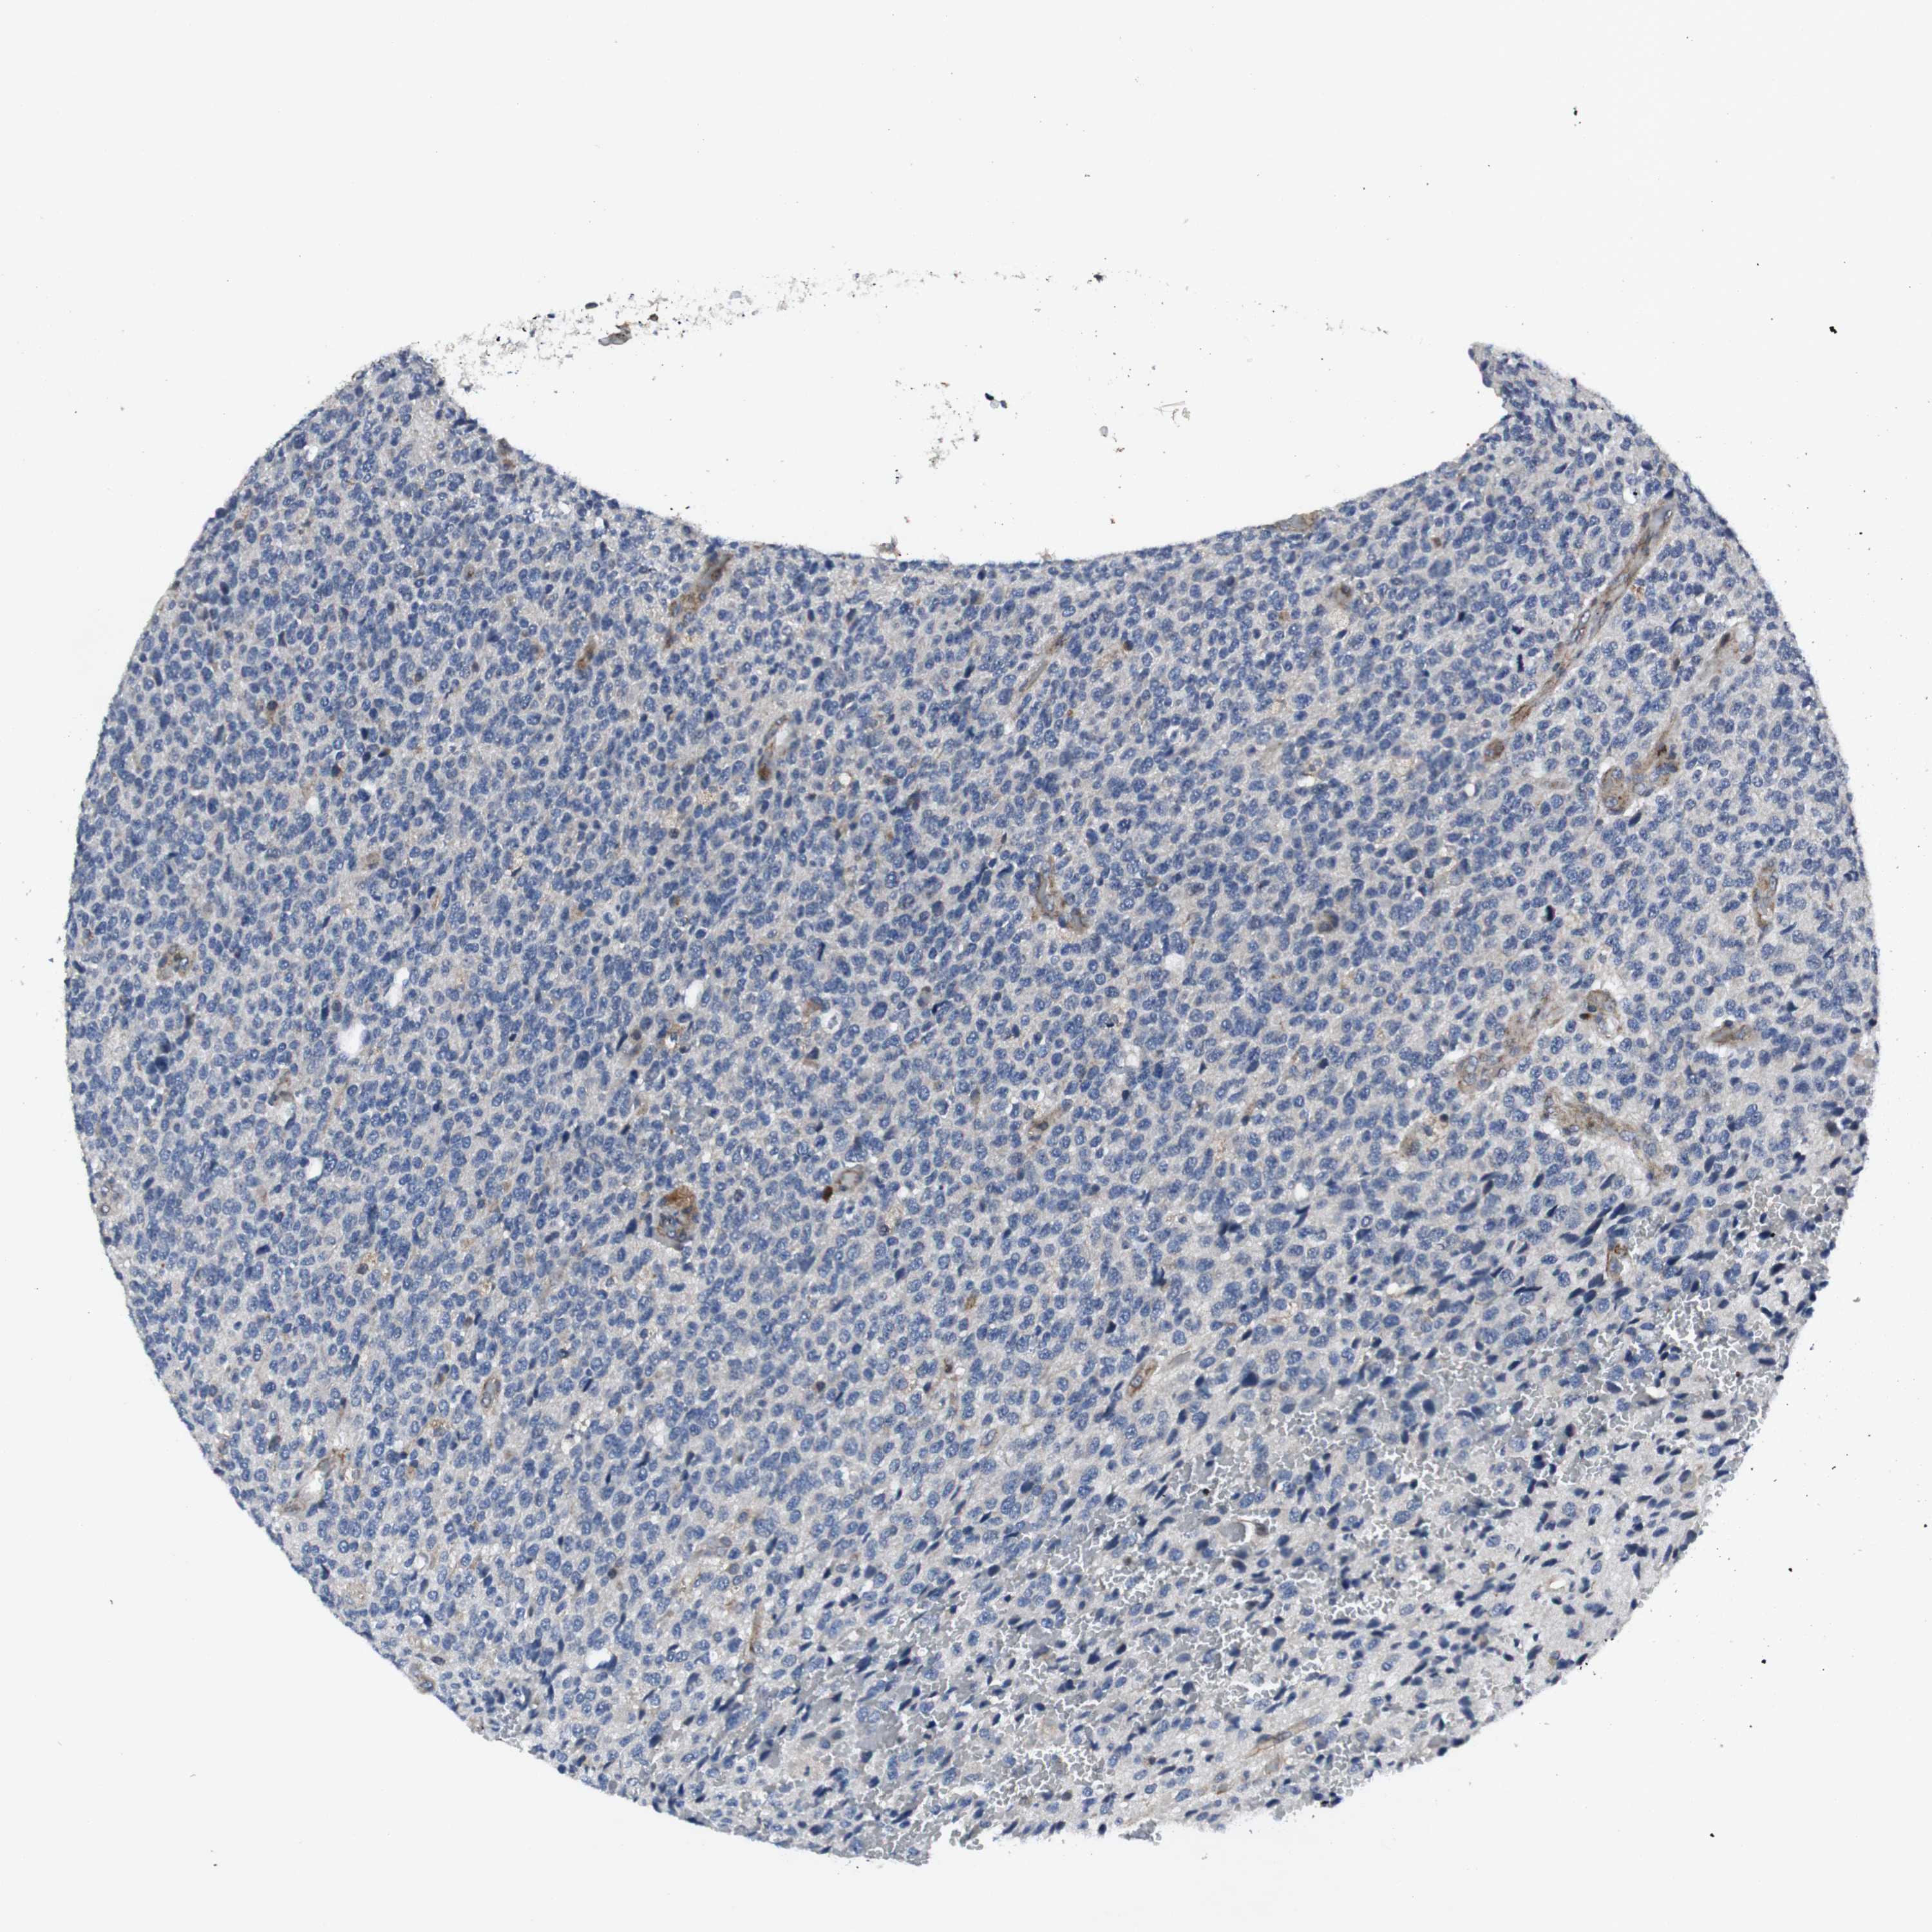

GLIOMA - Protein expressioni

A mouse-over function shows sample information and annotation data. Click on an image to view it in a full screen mode. Samples can be filtered based on level of antibody staining by selecting one or several of the following categories: high, medium, low and not detected. The assay and annotation is described here.

Note that samples used for immunohistochemistry by the Human Protein Atlas do not correspond to samples in the TCGA dataset.

Antibody stainingi

Antibody staining in the annotated cell types in the current human tissue is reported as not detected, low, medium, or high, based on conventional immunohistochemistry profiling in selected tissues. This score is based on the combination of the staining intensity and fraction of stained cells.

Each image is clickable and will lead to virtual microscopy that enables deeper exploration of all samples and also displays staining intensity scores, fraction scores and subcellular localization as well as patient and tissue information for each sample.

Antibody HPA001860

Antibody CAB013108

Staining

High

Medium

Low

Not detected

Intensity

Strong

Moderate

Weak

Negative

Quantity

>75%

75%-25%

<25%

None

Location

Nuclear

Cytoplasmic/membranous

Cytoplasmic/membranous,nuclear

Glioma, malignant, High grade

Glioma, malignant, Low grade